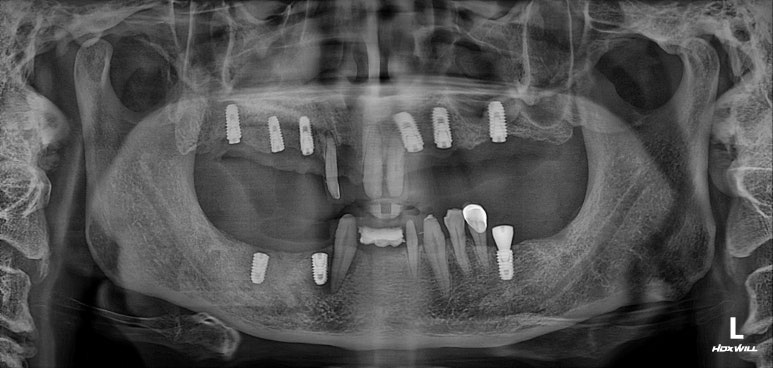

위턱 임플란트 수술을 하였습니다.

저희 치과의 수술 과정은 매우 심플합니다.

임플란트 1차 수술은 보통 두 번에 나누어 이루어집니다. 위턱 한 번, 아래턱 한 번.

이렇게 나누는 이유는 간단합니다. 임시 틀니 수정 과정을 간편하게 하기 위해서죠. 위/아래로 나누어야 임시틀니를 적응하는게 편해지실겁니다.

이제 임플란트를 모두 심어내었으니, 3개월 기다려야합니다.

임플란트 2차수술을 하였습니다.

3개월이 지나면, 본인의 잇몸뼈와 임플란트가 단단한 골유착을 형성합니다.

비교적 씹어먹을 수 있게 임플란트가 고정이 되었다는 말씀 !!

잇몸안에 묻혀있는 임플란트를 나중에 머리와 연결할 수 있도록, 통로를 만들어주는 임플란트 2차수술을 시행합니다. 잘 보시면 뭔가 더 길어진 것처럼 보이실거에요~